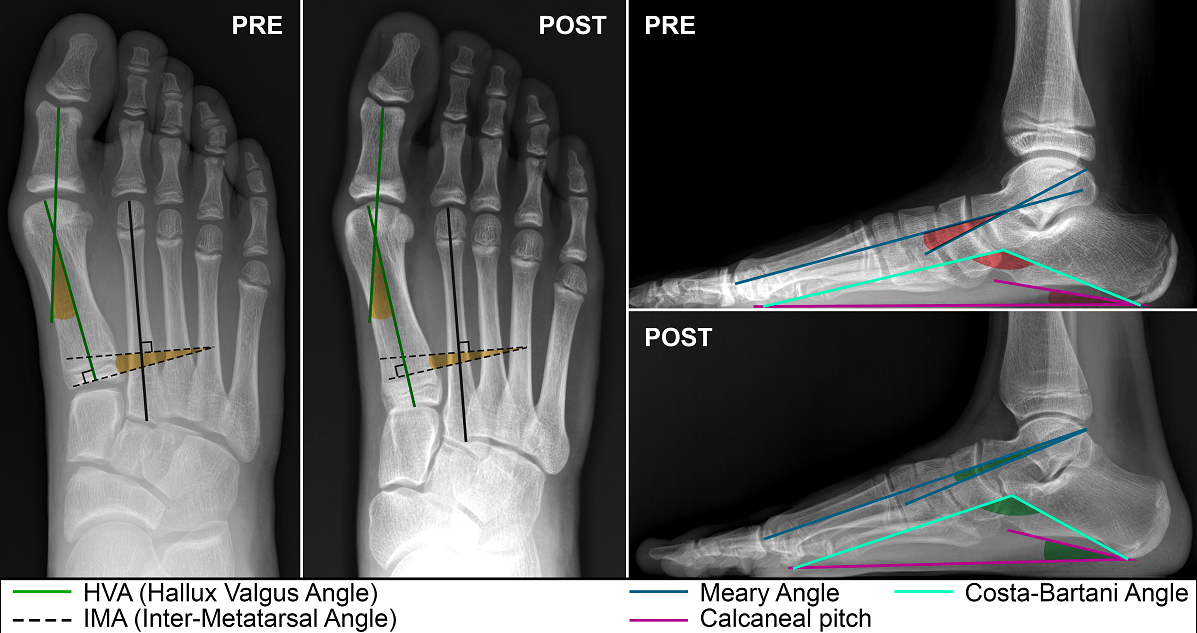

Introduction: Subtalar Arthroereisis (STA) is a surgical intervention for pediatric flexible flatfoot (PFF), primarily targeting hindfoot alignment by limiting excessive subtalar eversion. However, its effects on forefoot parameters remain underexplored. This study aims to investigate radiological changes following STA in pediatric patients. Materials and Methods: A retrospective analysis was conducted on consecutive patients treated with STA for PFF. First ray-related angles, including Hallux Valgus Angle (HVA) and Inter-Metatarsal Angle (IMA), alongside hindfoot radiological parameters such as Meary, Calcaneal Pitch, and Costa Bartani angles, were assessed. Subgroup analysis by gender was performed, and correlations between demographic and pre-operative radiological parameters were examined. Results: Forty-one patients (81 feet) with a mean age of 11.6 years were included, with a mean follow-up duration of 6.4 months. No significant differences were observed in first ray-related an-gles pre- and post-operatively, with mean IMA changing from 7.97° to 7.18° and mean HV angles from 9.51° to 8.66°. Noteworthy improvements were seen in flat foot angles, including Meary, Calcaneal Pitch, and Costa Bartani angles, postoperatively. Age subgroup analysis revealed similar trends in IMA and HVA changes between Group A (operated before peak growth) and Group B (operated later). Higher preoperative angles tended to improve, while lower preoperative IMA and HVA tended to worsen postoperatively, all remaining within normal ranges. Conclusion: STA showed positive radiological outcomes for PFF treatment, while negligible changes in first ray-related angles were observed. Age subgroup analysis indicated similar trends regardless of operation timing. Higher preoperative angles tended to improve, while lower preoperative angles tended to worsen postoperatively, despite all falling within non-pathological ranges. Further re-search is warranted to confirm this correlation.

The primary objective was to assess significant differences in forefoot radiological parameters pre and post-STA. HVA and IMA were measured on preoperative and 6-month follow-up radiographs under full weight-bearing conditions. Normal ranges for the parameters were defined as follows: HVA angles < 15° [8]; IMA angles < 9° [8].

The secondary aim was to observe hindfoot radiological parameters modifications after STA, measuring Meary's Angle (MA), Calcaneal Pitch angle (CP), and Moreau Costa Bertani angle (MCB) on pre-operative and 6-month follow-up radiographs. Normal ranges for the parameters were defined as follows: MA [9] between -4° and +4°; CP [9] angle between 18 and 20°; MCB [10] angle between 115 and 125°.

Concerning the measurements of first ray-related angles, no significant difference was observed between the preoperative and postoperative measurements (Table 1).

Regarding hindfoot related angles, Meary, Costa Bartani e calcaneal Pitch showed an improvement but no significant difference was observed between the preoperative and postoperative measurements (Table 1).